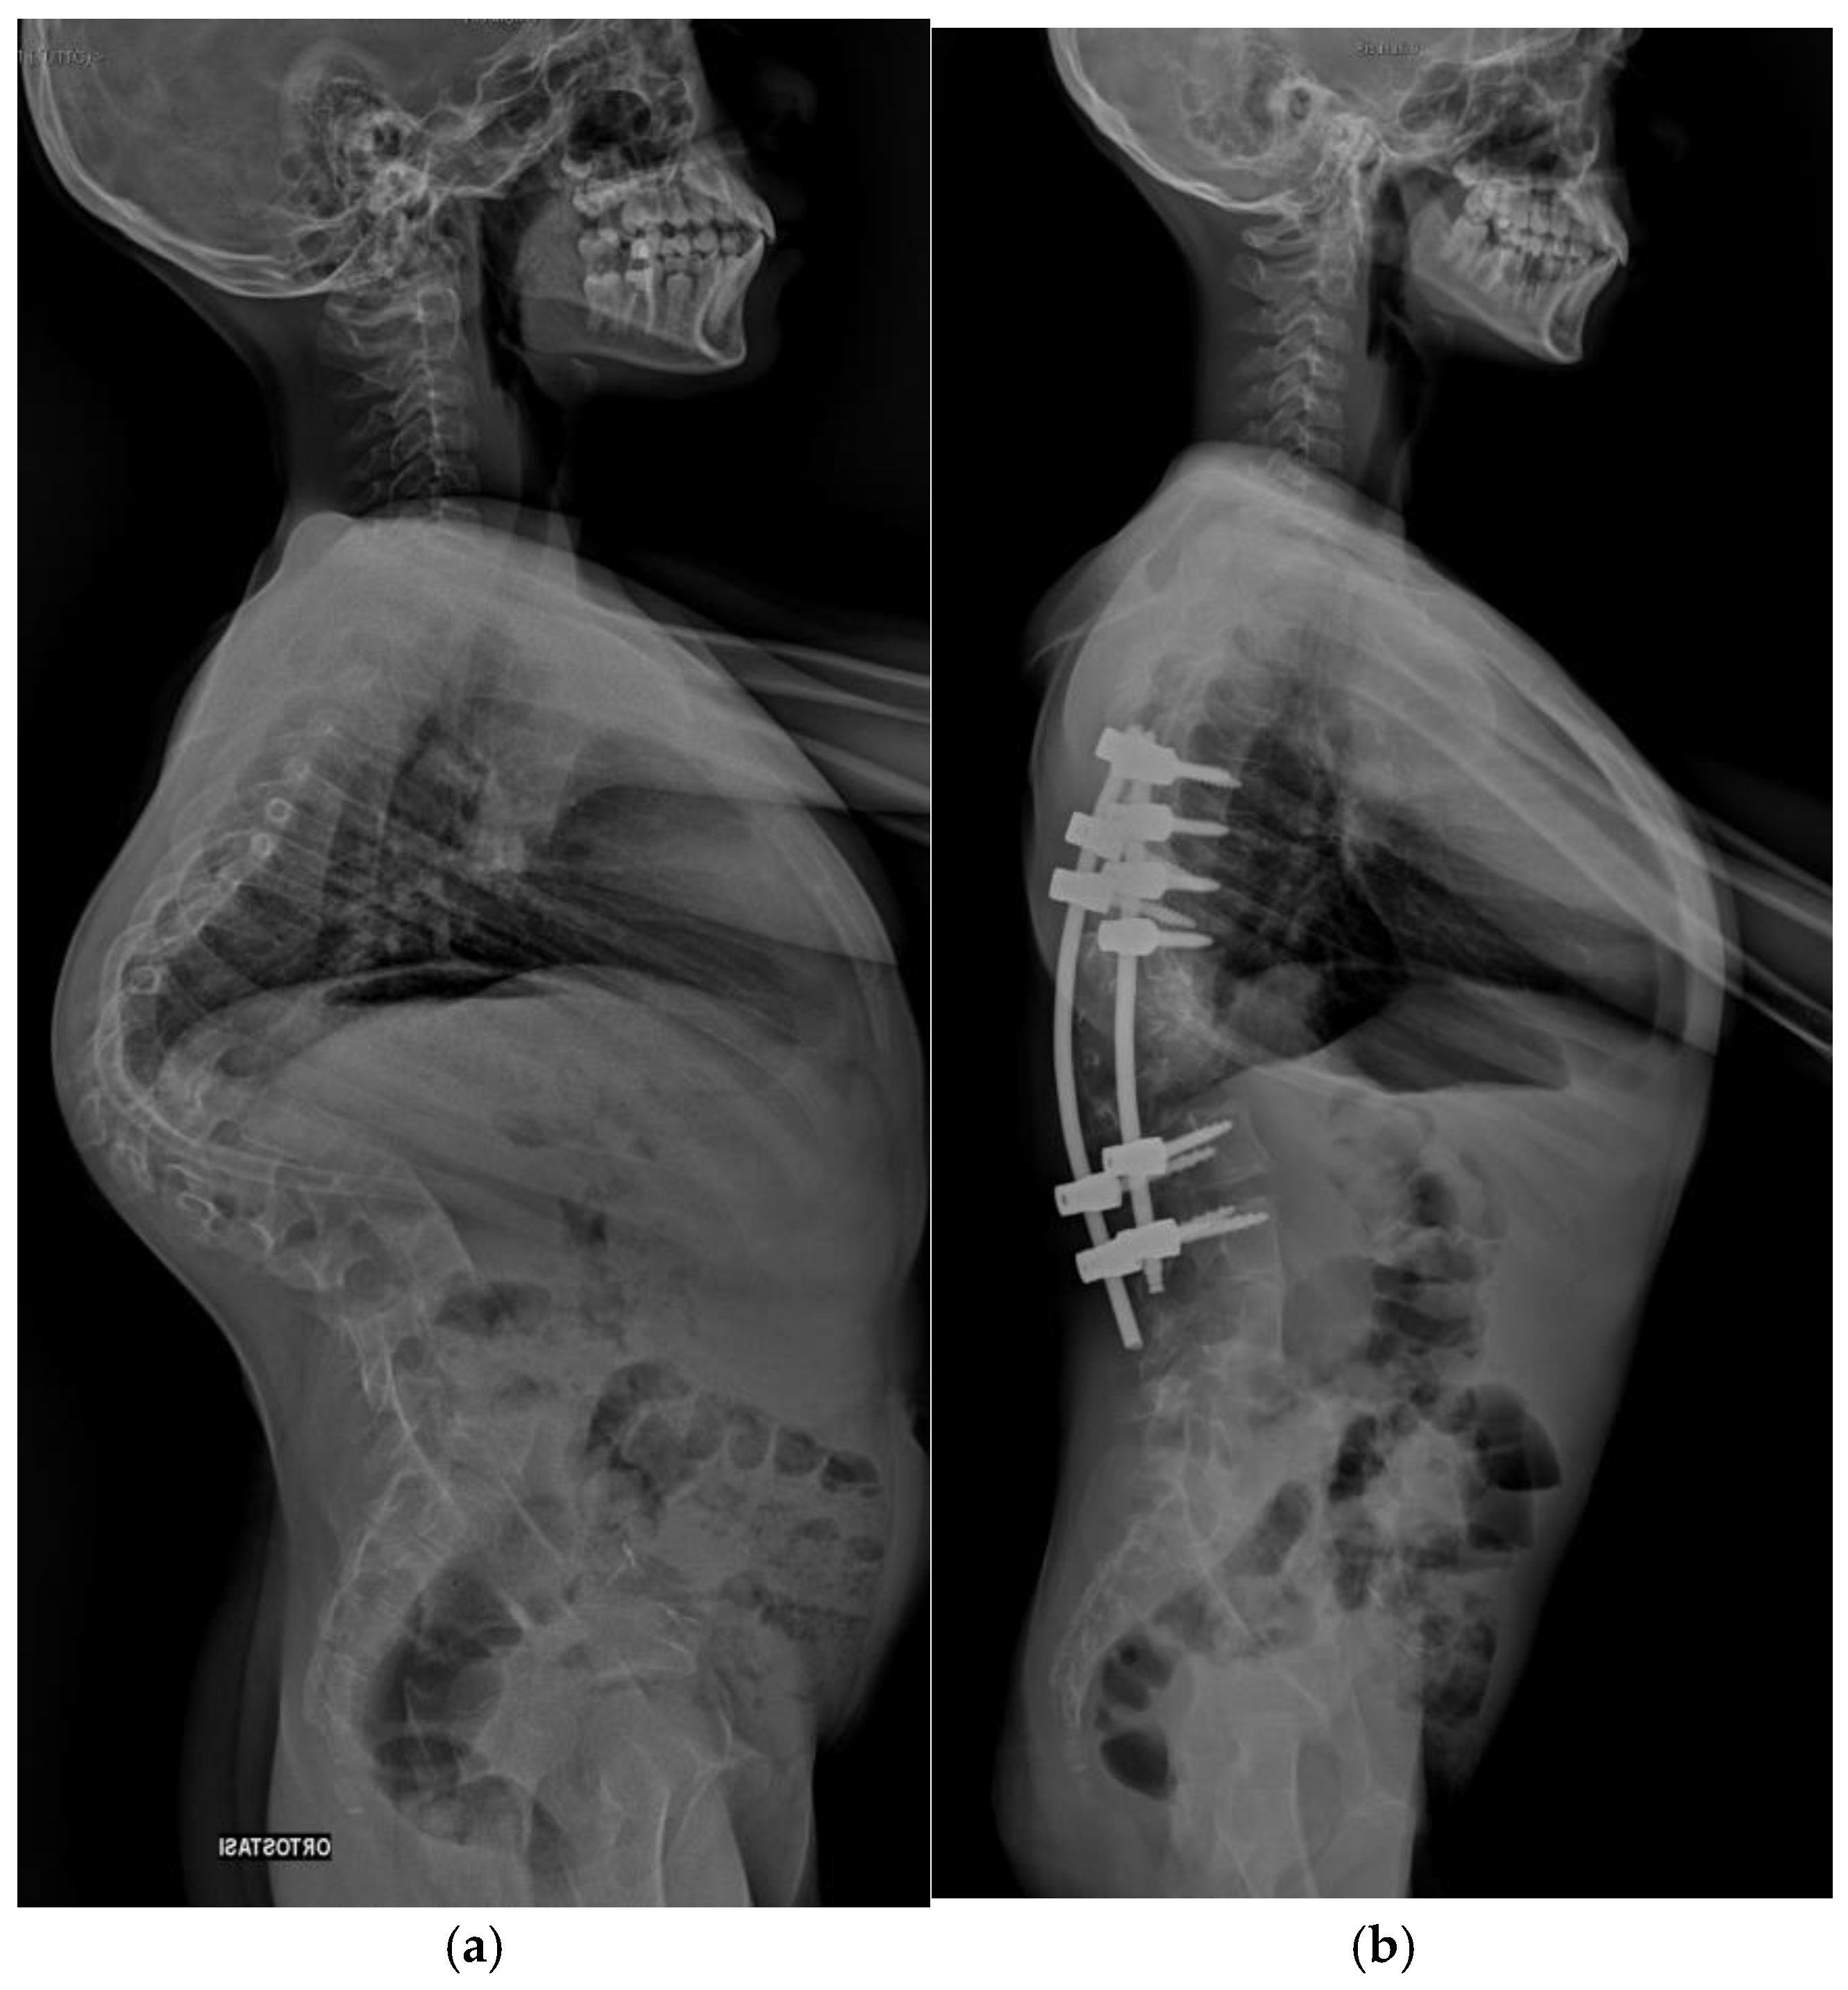

Pre-operative and post-operative radiographs documenting case 2 are reported in Figure 2 and Figure 3.

Figure 2. Antero-posterior radiograph of Patient 2. (a) Preoperative assessment. (b) Postoperative assessment.

Jcm 14 00374 g002

Figure 3. Lateral radiograph of Patient 2. (a) Preoperative assessment. (b) Postoperative assessment.

A 14-year-old male, weighing 28 kg and measuring 126 cm in height (BMI: 17.6), presented with right-convex congenital kyphoscoliosis, with predominant kyphotic deformity. Imaging revealed hemivertebrae from D10 to L2 and butterfly vertebrae at D9, L2, and L3, along with rib hypoplasia and a bifid rib branch. The patient had not undergone any prior surgical intervention or conservative treatment before surgical evaluation.

Postoperative Course

The postoperative course was uneventful, and the patient did not experience any complications. The preoperative hemoglobin was 13.6 g/dL, and following a single intraoperative transfusion, the hemoglobin level was 10.4 g/dL at discharge. Preoperatively, the patient had a thoracic kyphosis of 74° Cobb, which was reduced to 18° postoperatively. At the last follow-up, 1 year and 7 months after surgery, the patient reported no pain and demonstrated good coronal and sagittal balance both clinically and radiographically.